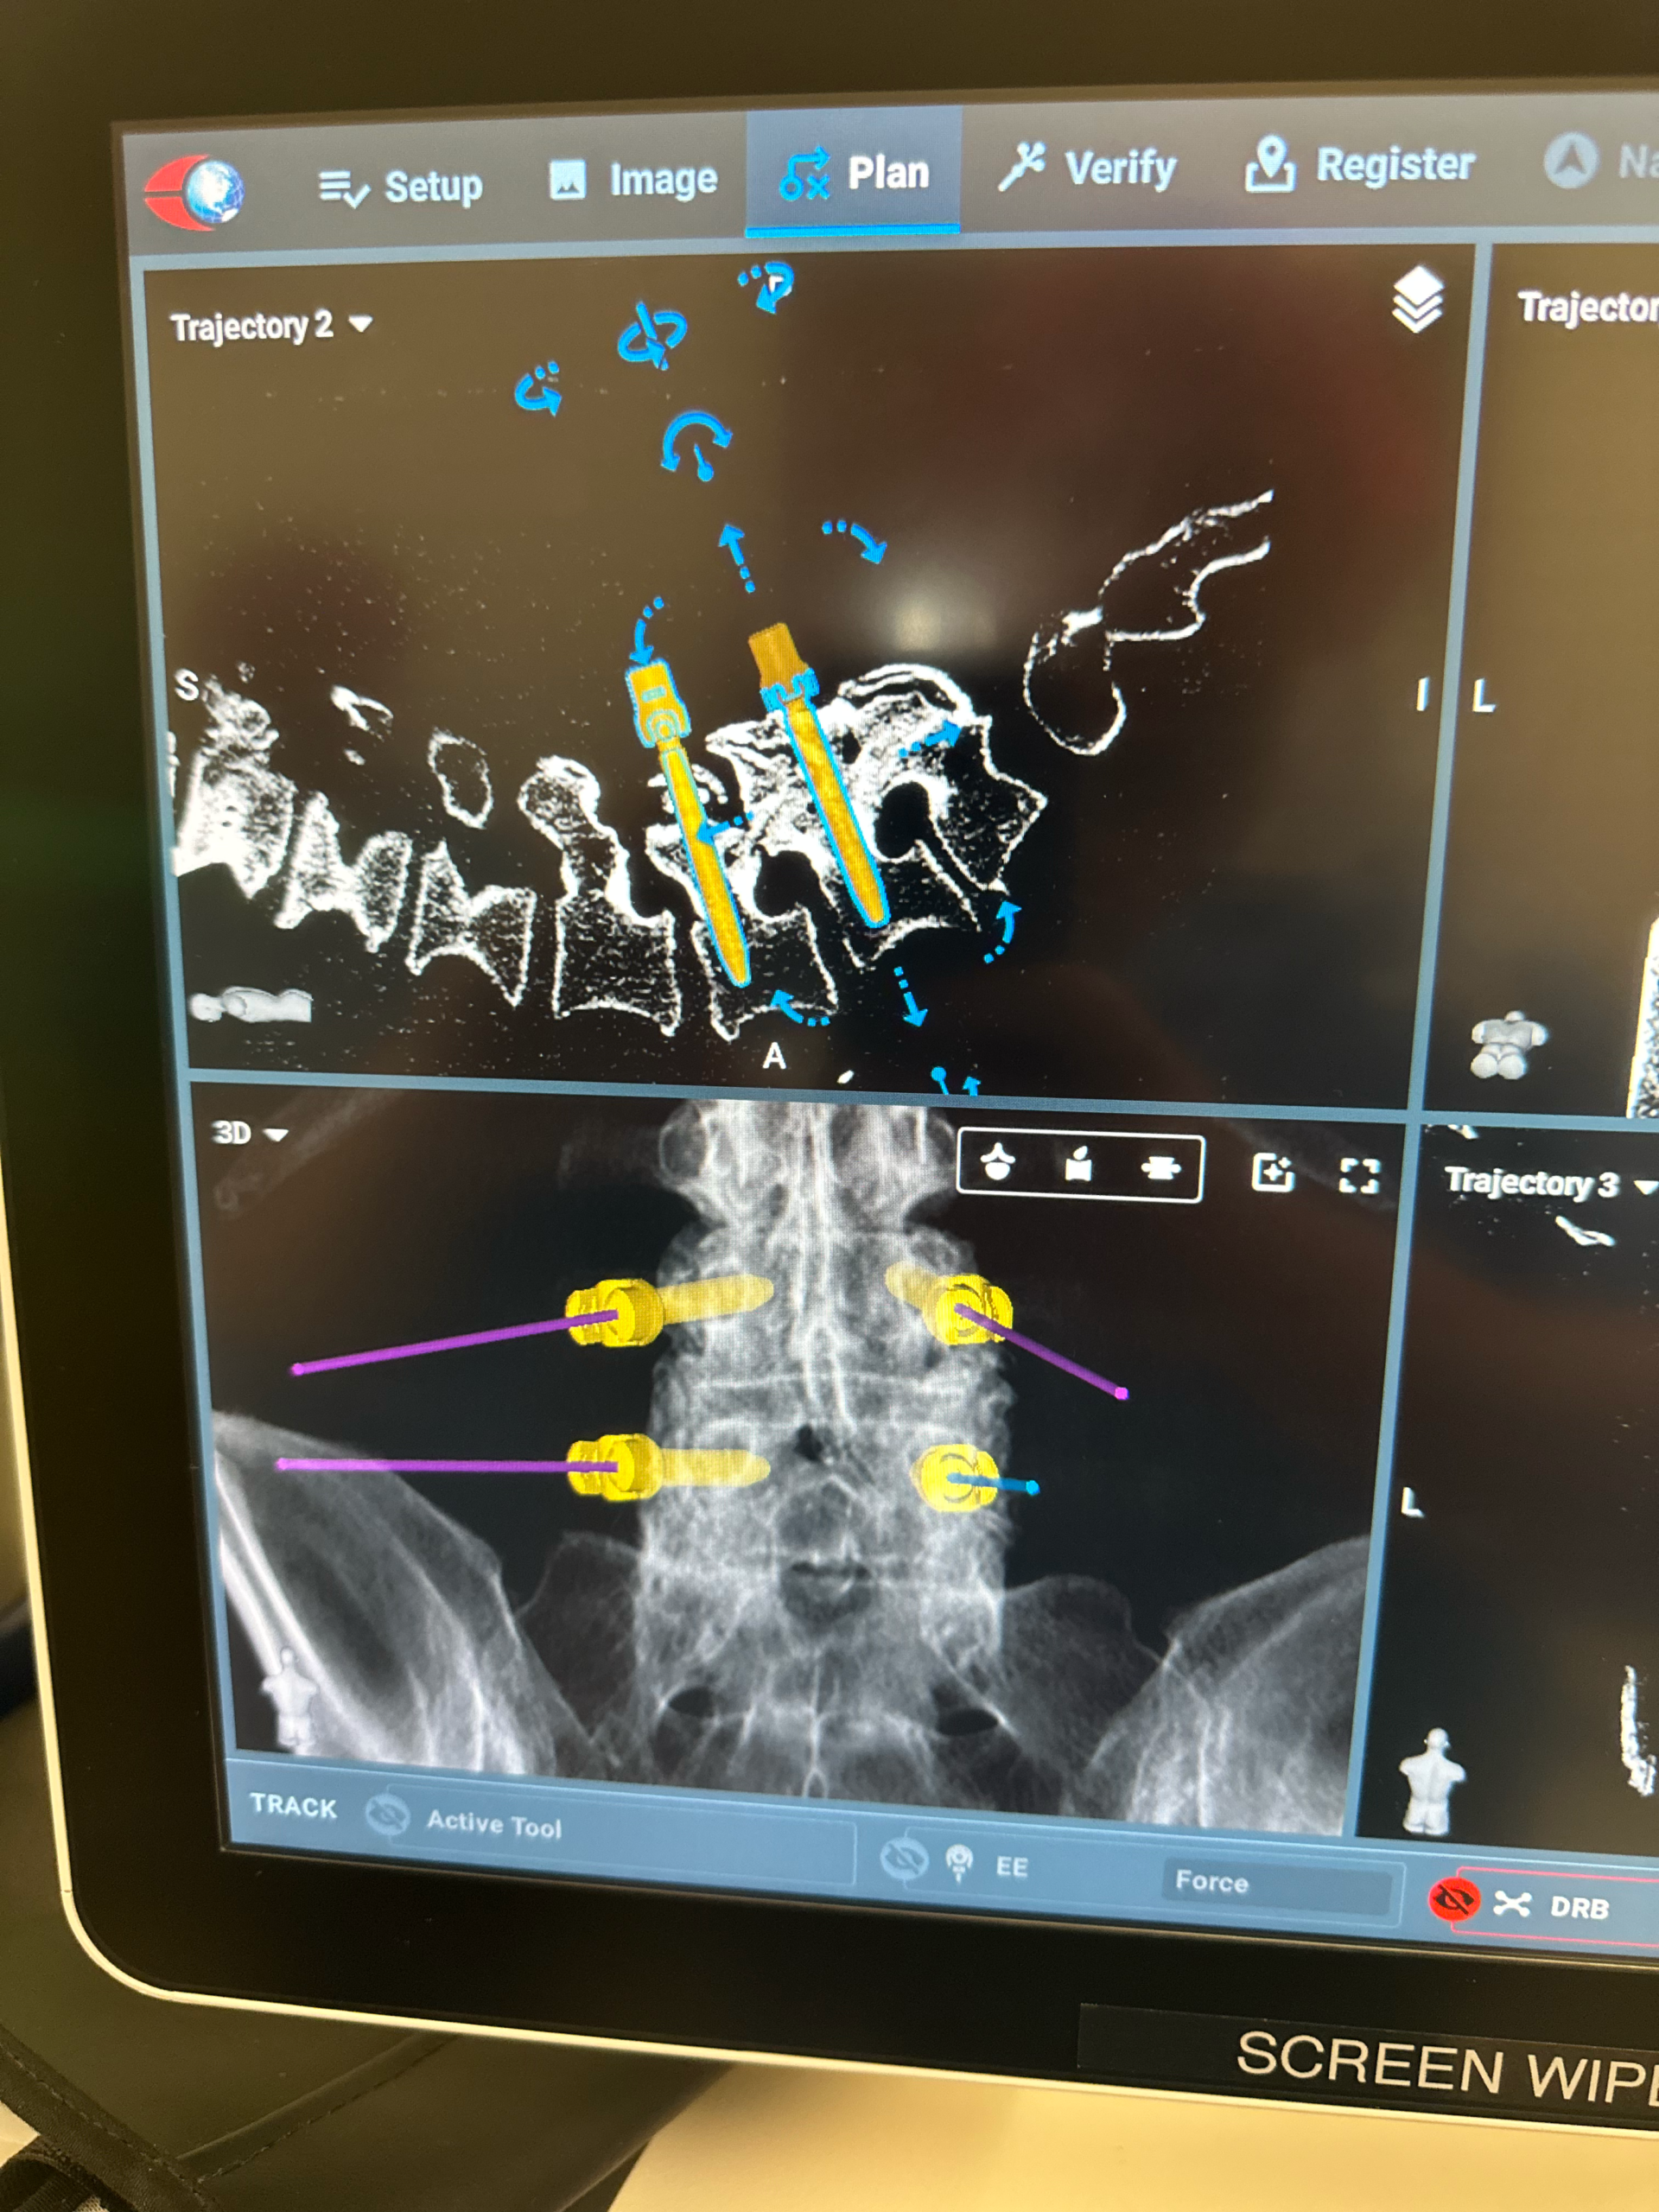

Lumbar disc replacement

Lumbar disc replacement

- TOPS Procedure with robotic guidance